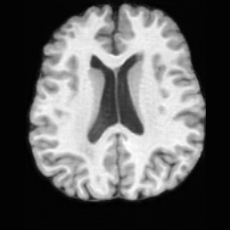

(a)PathologicalInput ImageSynthSR [18]Brain-ID [28]UNA [30]USBHealthyGround TruthRefer to captionRefer to captionRefer to captionRefer to captionRefer to captionRefer to captionRefer to captionRefer to captionRefer to captionRefer to captionRefer to captionRefer to captionRefer to captionRefer to captionRefer to captionRefer to captionRefer to captionRefer to captionRefer to captionRefer to captionRefer to captionRefer to captionRefer to captionRefer to caption(b)HealthyInput ImageConditionalLesion MaskUNA [30]USBRefer to captionRefer to captionRefer to captionRefer to captionRefer to captionRefer to captionRefer to captionRefer to captionRefer to captionRefer to captionRefer to captionRefer to captionRefer to captionRefer to captionRefer to captionRefer to caption

Figure 5: Comparison of bidirectional brain editing. (a) pathology-to-healthy, the circles and arrows highlight lesion regions and unsuccessful reconstructions; (b) healthy-to-pathology. Note that SynthSR and Brain-ID cannot perform healthy-to-pathology editing.

Healthy-to-Pathology Editing. As shown in Fig. 5 (b), given a healthy brain image paired with a random lesion mask, USB seamlessly embeds the lesion into the healthy anatomy, producing realistic pathological appearances consistent with surrounding structural context. Yet UNA’s syntheses are visually unrealistic, with the conditioned lesion mask simply overlaid as a parallel layer onto the healthy brain. Tab. 3 further demonstrates USB’s superior performance. The evaluation was conducted on 100 pairs of lesion masks and healthy brains, with real stroke images